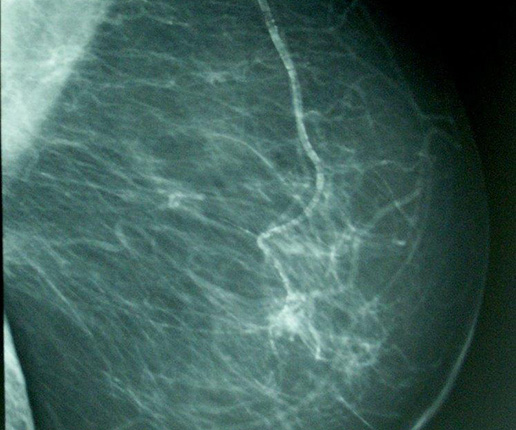

Streszczenie Wpracy przedstawiono techniki pozycjonowania w badaniu mammograficznym. Omówiono przygotowanie do badania oraz jego realizację w projekcjach podstawowych oraz dodatkowych, diagnostycznych. Zwrócono uwagę na procedury oraz błędy, których należy unikać. Słowa kluczowe: mammografia, pozycjonowanie Abstract The techniques of positioning in mammography, were presented in the article. The preparation for examination and as its realization in views considered as a gold standard as…

WorkstationOne to oprogramowanie dedykowane dla radiologów opisujących obrazy mammograficzne. Różni się od pozostałych rozwiązań tego typu tym, że zostało zaprojektowane przez lekarzy. Przebieg pracy w WorkstationOne został skonsultowany z czołowymi radiologami z wielu regionów świata, co znacznie usprawniło cały proces i dzięki czemu przechodzenie pomiędzy ważnymi w ocenie obszarami obrazu jest bardzo płynne. Lekarz prowadzony jest od momentu wczytania badania, poprzez ocenę obrazów, aż po utworzenie…